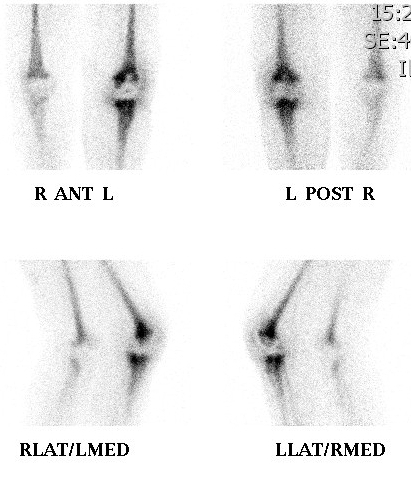

8. Avascular necrosis

Ischaemic bone cold, surrounding bone hot

- doughnut appearance in hip